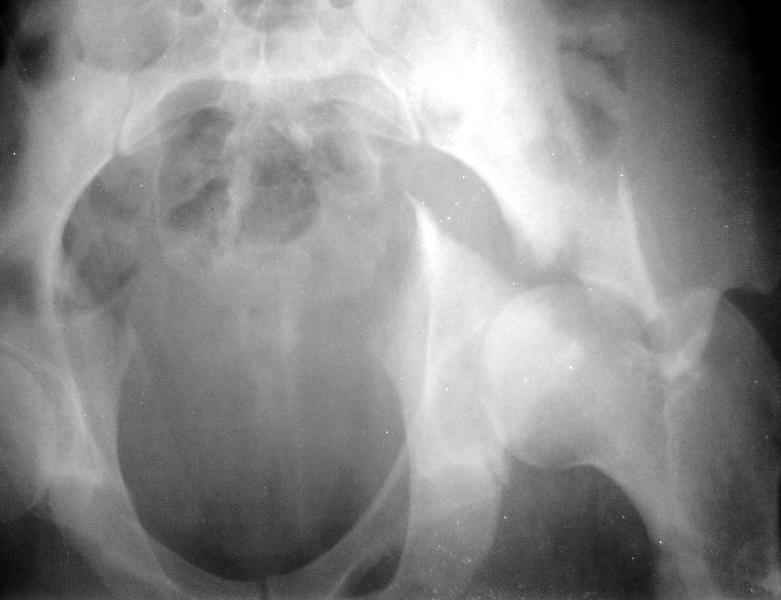

Сегодня на приеме был пациент, чьи начальный снимок напомнил обсуждаемый сейчас (см. выше). Снимки в других проекциях, показывающие истинный характер повреждения, ниже. Это inlet проекция (вход в таз) и запирательная проекция Judet.

Травма 17 ноября 2002 г., поступил к нам 1 декабря, оперирован 8-го - открытая репозиция, остеосинтез пластинками и винтами. Учитывая повреждение переднего полукольца справа, и крестца и крестцово-подвздошного сочленения слева, наложили аппарат на 2 месяца.

Для экономии места привожу интра- и послеоперационный обзорный снимок, без дополнительных проекций.